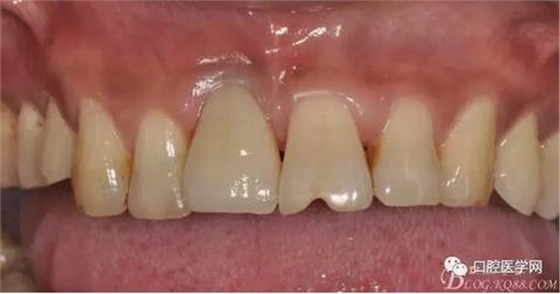

圖19 口內修復基臺正位照

圖20 口內修復基臺正位照